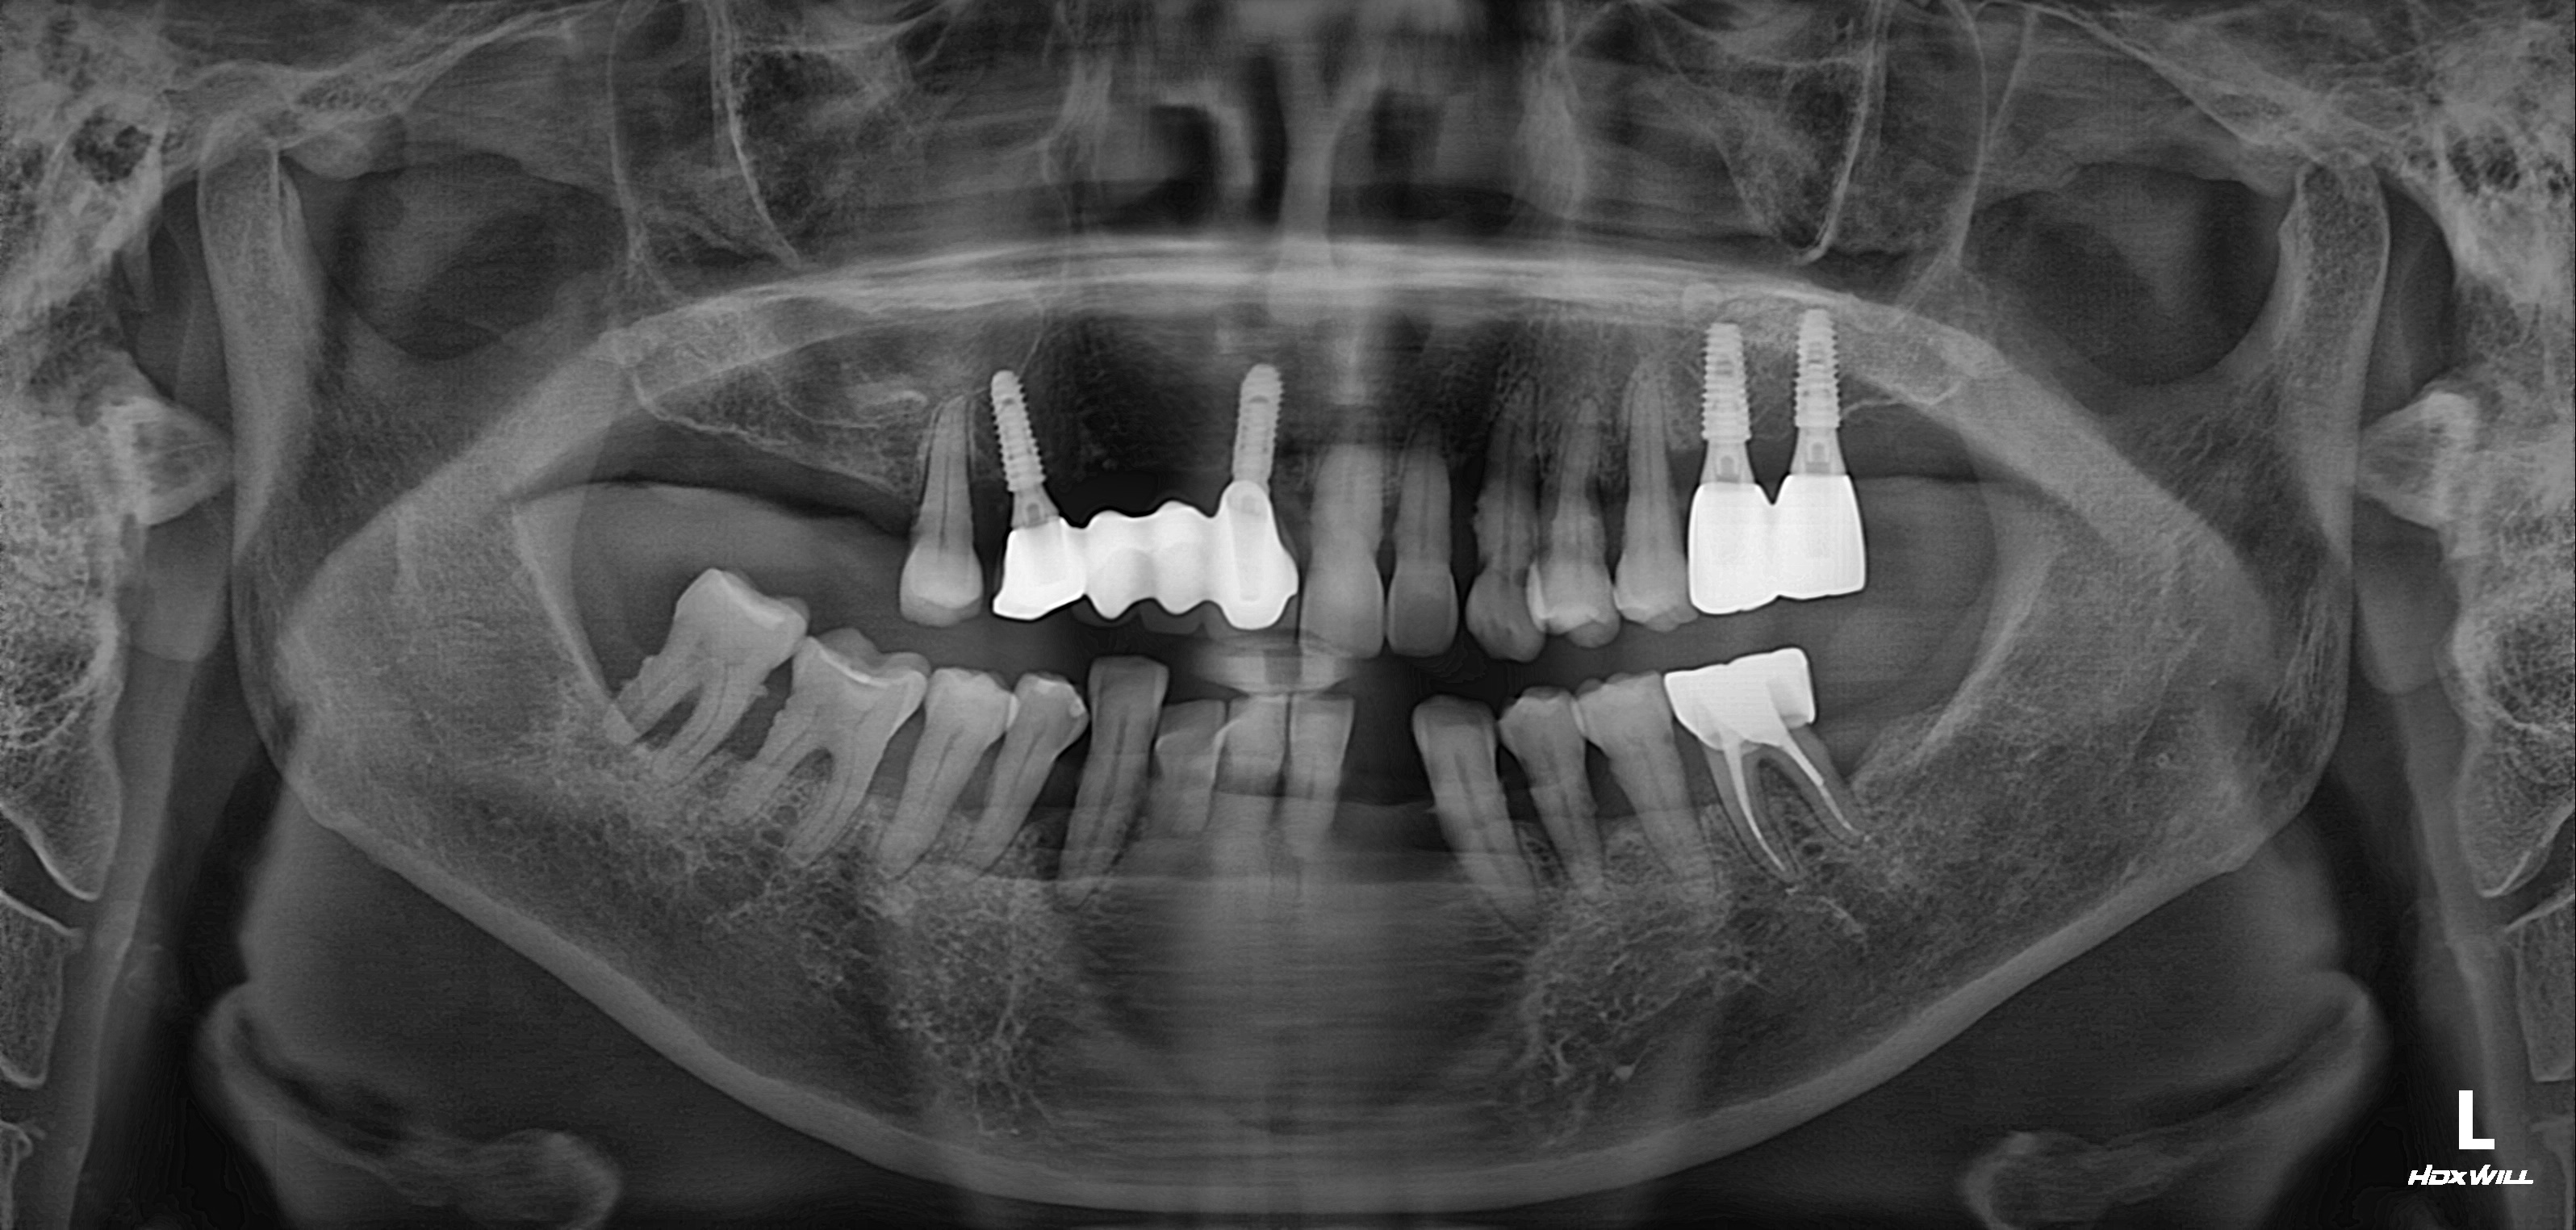

하악 전체+상악 구치부 임플란트 식립사례